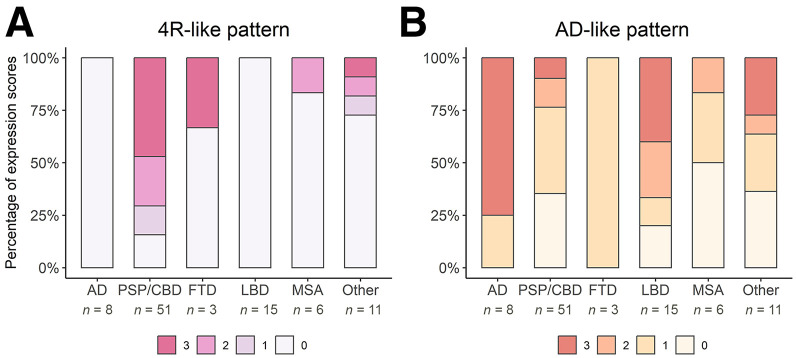

Visual Ratings of [18F]Florzolotau PET Binding

Figure 2 depicts representative transaxial slices of average [18F]florzolotau PET images of each group. Figure 3 and Supplemental Table 1 illustrate the proportion of visual ratings for 4R-like or AD-like patterns in the different patient groups. The 3 raters reached substantial agreement for the classification of 4R-like (κ range, 0.78–0.97) and AD-like (κ range, 0.88–0.96) patterns (higher agreement between more experienced raters, 0.97 vs. 0.84).

The expected 4R-like pattern from the literature was replicated by the present sample (Fig. 2). This 4R-like pattern was more highly prevalent (84.3%) and expressed (mean score, 2.0 ± 1.1) in the PSP/CBD group than in all other disease groups (pooled prevalence, 11.6%; mean score, 0.26 ± 0.75; P < 0.0001 compared with the 4R group). The pattern was observed in most PSP/CBD cases with moderate to strong expression (12/51 [23.5%] and 24/51 [47.1%], respectively), whereas only few patients with PSP/CBD showed no or mild pattern expression (8/51 [15.7%] and 7/51 [13.7%], respectively). Consensus ratings did not significantly differ between patients without CBS (2.2 ± 1.1) and with CBS (1.5 ± 1.2, P = 0.08). However, the gradient of binding was significantly different: patients with PSP/CBD without CBS (PSP, according to consensus diagnoses) showed more pronounced subcortical binding (gradient rating, 0.3 ± 0.7), whereas those with CBS exhibited more cortical binding (gradient rating, 1.6 ± 0.5; P < 0.0001).

In turn, the 4R-like pattern was not detected in any AD and LBD cases. One of 3 (33.3%) FTD cases was rated to show a strong 4R-like pattern (not present in the remaining 2 cases), whereas only 1 of 6 (16.7%) MSA cases showed moderate 4R-like pattern expression (not present in the remaining 5 cases). Three of 11 patients with other diagnoses were rated as showing a mild, moderate, and strong 4R-like pattern (final diagnoses of nonneurodegenerative disease, subcortical leukoencephalopathy, and nonneurodegenerative disease, respectively).

The AD-like pattern was also well replicated in the present sample (Fig. 2). Consensus ratings indicated strong and mild AD-like pattern expression in 6 of 8 (75.0%) and 2 of 8 (25.0%) patients, respectively (i.e., prevalence of 100% and mean score of 2.5 ± 0.9 in the AD group). The AD-like pattern was also frequently present in other patient groups (pooled prevalence, 67.4%), albeit at a lower magnitude (mean score, 1.2 ± 1.1; P < 0.01 compared with the AD group): moderate and strong AD-like pattern expression was rated in a substantial fraction of LBD cases (moderate, 4/15 [26.7%], 3/7 PD and 1/4 PDD; strong, 6/15 [40.0%], 2/4 PDD and 4/4 DLB) and a few PSP/CBD cases (moderate, 7/51 [13.7%]; strong, 5/51 [9.8%]; at higher frequency in patients with CBS [6/13] than without CBS [6/38]). The remaining LBD (5/15 [33.3%], 4 PD and 1 PDD), PSP/CBD (39/51 [76.5%]), FTD (3/3), and MSA (except 1/6 with moderate pattern expression) patients showed no or mild AD-like pattern expression (Fig. 3). In patients with other diagnoses, AD-like pattern ratings were roughly equally distributed across the 4 grades (Fig. 3).

The ROC analysis for the consensus score of the 4R-like pattern (PSP/CBD vs. all other patients) revealed AUC of 0.87 (95% CI, 0.80–0.94; range of the 3 raters, 0.78–0.87; highest in experienced raters). The optimal threshold for delineating PSP/CBD from all other disease groups was a score of at least 1 (i.e., at least mild 4R-like pattern), leading to a sensitivity of 84.3% (71.4%–93.0%) and a specificity of 88.4% (74.9%–96.1%). The positive predictive value was 89.6% (77.2%–95.5%), and the negative predictive value was 82.6% (68.8%–93.9%). When stratified in PSP/CBD without and with CBS, ROC analyses yielded comparable AUC (0.89; 95% CI, 0.82–0.96; and 0.82; 95% CI, 0.69–0.95, respectively; Delong test, P = 0.39). When focusing on proper parkinsonian syndromes (i.e., PSP/CBD vs. LBD and MSA), the ROC AUC was also largely unchanged (0.91; 95% CI, 0.85–0.97; P = 0.46).

The AD-like pattern did not support the distinction of patients with PSP/CBD alone (AUC, 0.36; range, 0.25–0.47), nor did it improve the distinction in combination with the 4R-like pattern (logistic regression; AUC, 0.88; range, 0.81–0.95; factor AD-like pattern; P = 0.53). Conversely, exclusion of AD cases from the aforementioned analysis concerning the discrimination of PSP/CBD did not affect overall diagnostic performance (AUC, 0.86; range, 0.78–0.94; P = 0.83). Despite the limited AD sample size and the diversity of other diagnoses, the AD-like pattern effectively distinguished the AD group from all other disease categories, achieving AUC of 0.82 (0.68–0.96).

Finally, the rating of the binding gradient of the 4R-like pattern allowed an accurate distinction between patients with and those without CBS in PSP/CBD patients who exhibited a 4R-like pattern (43/51; ROC AUC, 0.89; ROC AUC range, 0.80–0.98). In addition, 27 of 33 (81.8%) patients without CBS showed subcortical dominant binding, whereas all patients with CBS exhibited balanced or cortical dominant binding.

The present study was conducted in a real-world sample of patients with parkinsonism that reflects the expected indication for tau PET in the clinical routine. It demonstrates that a visually rated 4R-like binding pattern on [18F]florzolotau PET allows the identification of patients with PSP/CBD with high sensitivity and specificity. In addition, a gradient of the 4R-like pattern toward cortical binding was highly associated with the presence of CBS in patients with a 4R-like pattern. Although the AD-like pattern of [18F]florzolotau binding as a marker of (early) AD copathology or possibly primary age-related tauopathy was common in this representative clinical cohort, it did not significantly affect the diagnostic performance of the 4R-like pattern.

Visual evaluation of the 4R-like pattern revealed ROC AUC of 0.87 for the discrimination of PSP/CBD from all other groups, which remained largely unchanged when focusing on proper parkinsonian syndromes (0.91) or excluding all AD patients (0.86). This aligns well with previous findings, which showed AUC between 0.87 and 0.94 for a volume-of-interest–based approach to separate PSP from α-synucleinopathies with [18F]florzolotau PET (ref. 1), and it suggests that the high specificity in this representative sample (88%) is not driven by easy identification of AD-related syndromes. This study validates promising earlier data in a larger clinical cohort that includes not only or predominantly patients with probable or later-stage PSP or PSP-RS and somewhat artificial controls (e.g., AD or healthy controls). Instead, the present sample appropriately covers the entire spectrum of syndromes and diagnoses that would be expected in parkinsonism with possible 4R tauopathies based on clinicopathologic studies (as explained in the introduction). Moreover, current estimates for sensitivity (84%) and specificity (88%) of the 4R-like pattern on [18F]florzolotau PET suggest an advantage in comparison to the second-generation ligand [18F]PI-2620, which allows detection of PSP-RS with high sensitivity (85%, at 77% specificity), whereas non–Richardson-type PSP (65%) and Aβ-negative CBS (65%) were detected with noticeably lower sensitivity (ref. 2,ref. 4). The mean disease duration of patients with PSP enrolled in the aforementioned studies (ref. 1,ref. 2) was longer (4.1 and 3.8 y) than that of the current PSP/CBD group (3.2 y), highlighting the possible value of [18F]florzolotau for earlier diagnosis. Moreover, the simple acquisition protocol and the easy-to-implement workflow for visual image analysis provide practical advantages compared with [18F]PI-2620 (60-min acquisition and kinetic modeling) (ref. 2). Cases of FTD and MSA with 4R-like pattern expression (1 patient each) are in line with the previous literature and may be related to the occurrence of 4R tau pathology in nonfluent variant primary progressive aphasia and behavioral variant FTD (ref. 26,ref. 27) or to misclassification because of possible off-target binding of [18F]florzolotau in MSA (ref. 28).